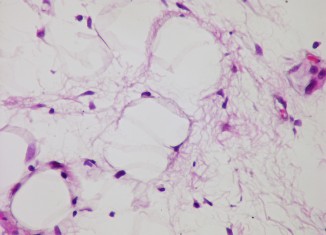

Before we go into the details of products that can be used for curing Lipoma, we should first know what the Lipoma is. Lipomas...